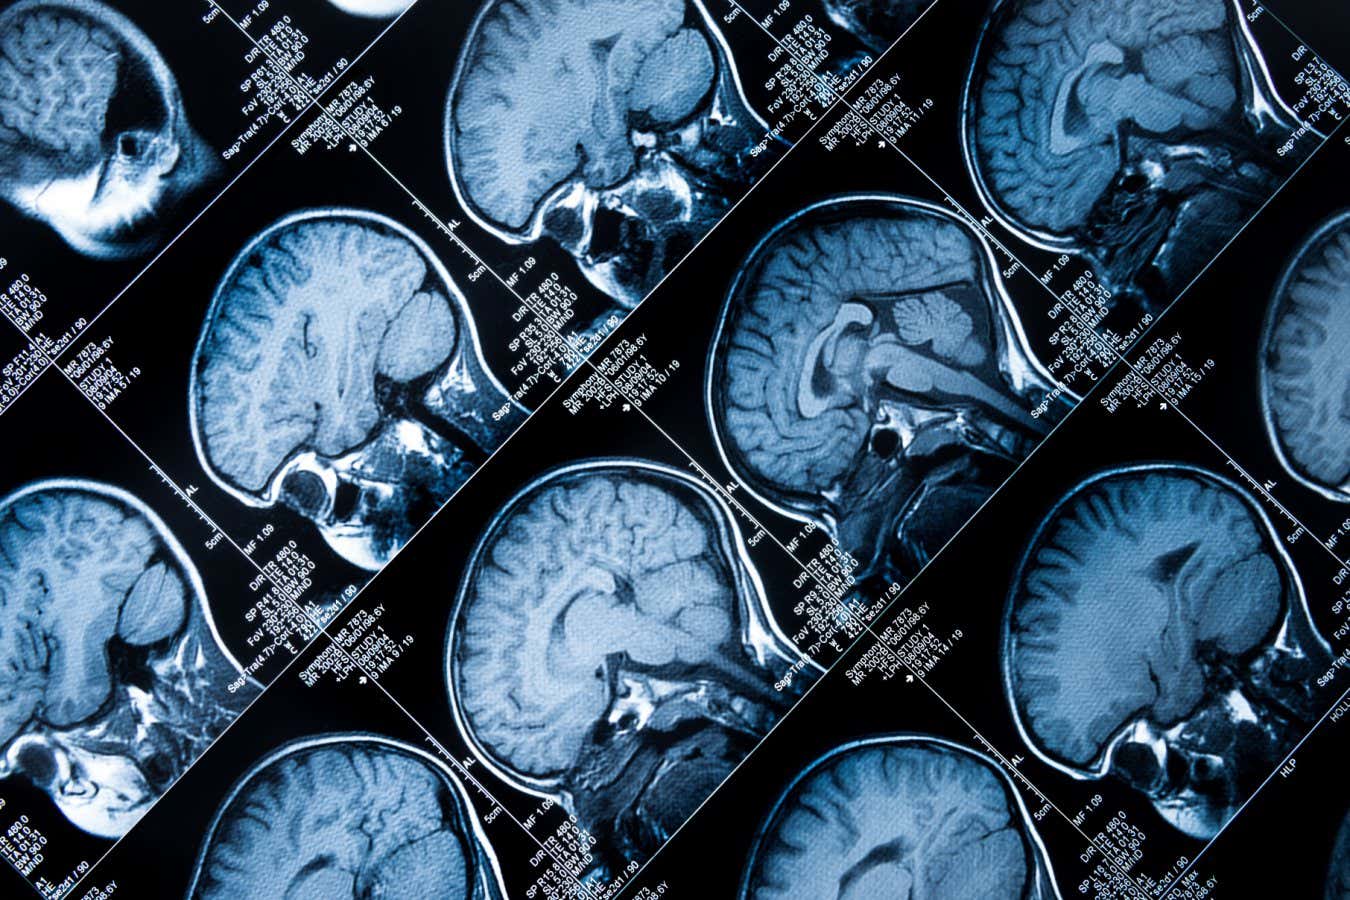

Two stories this week exemplify this. Almost all of us will be infected by the Epstein-Barr virus at some point in our lives, but, as we report here, genetic variants mean some of us are less able to expel it from our bodies. This may help explain why the virus is harmless to most people, but may be behind autoimmune conditions such as multiple sclerosis in some. Likewise, some people are resilient to the misfolded proteins that would otherwise cause Alzheimer’s disease.

Understanding these disease processes – and ultimately intervening in them – requires us to understand the complexity and diversity of human biology. It means gathering huge volumes of data on everything from people’s DNA to their immune systems, and figuring out the mechanisms at work in different people.